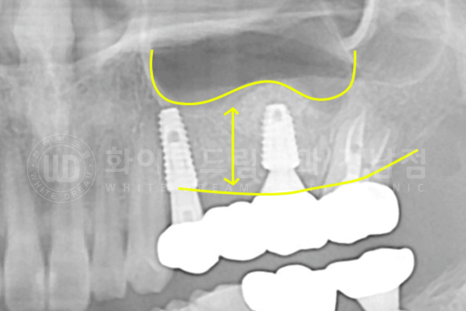

▲ lateral 술식을 이용하여 식립된 26번 임플란트입니다.

상악동 거상술 + 1차 수술 + 2차 수술을 한 번에 진행했고,

가루로 되어 있는 이식재가 주변 잇몸뼈와 잘 융합되는 회복 기간을 6개월 정도 가지기로 했습니다.

▲ 6개월의 회복 기간 후 보철 제작에 들어갔고 최종 보철 세팅 후 x-ray입니다.

수술 전과 후의 잇몸뼈 두께를 보면 차이점이 한눈에 확인되실 겁니다. ^^

동일 인물이며, 동일 환경에서 촬영되었습니다.

치료 기간 : 16.10.25 - 17.05.19